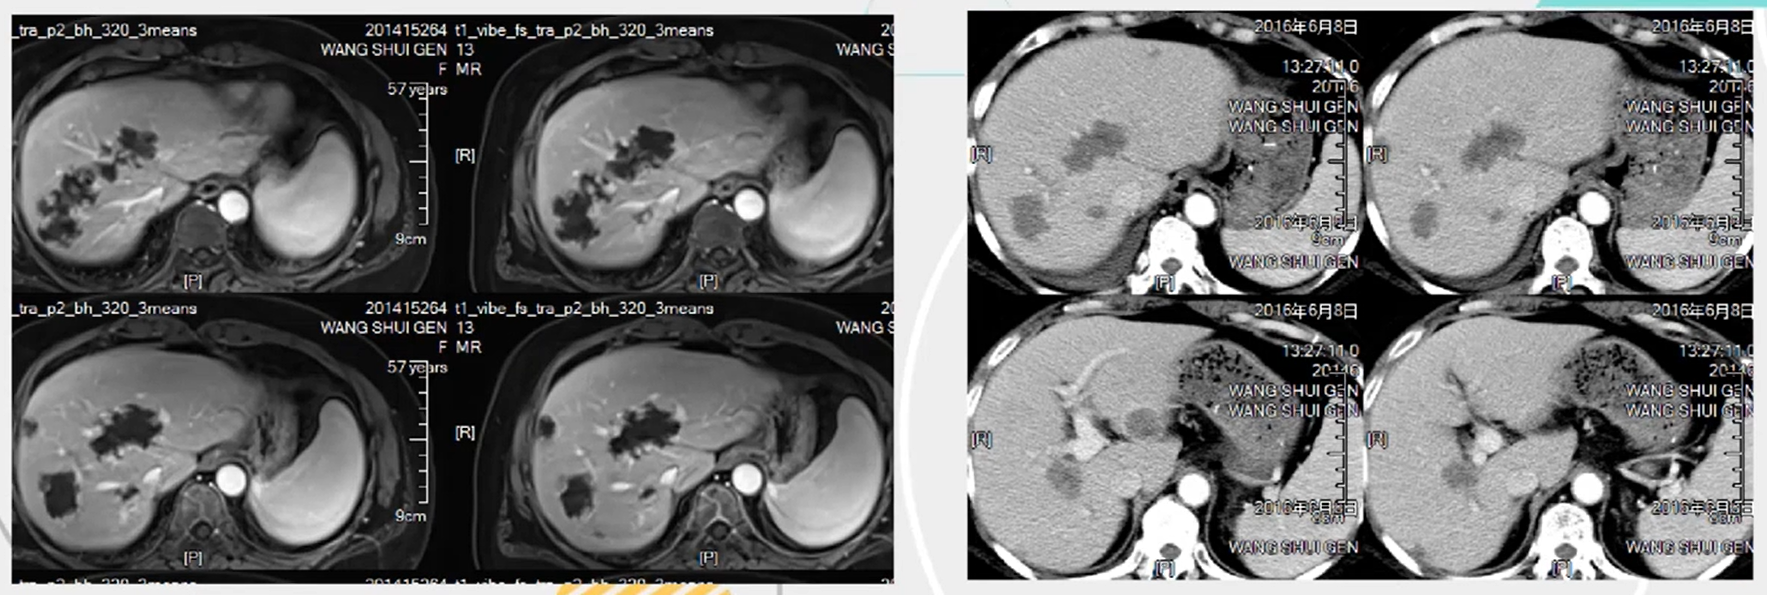

医学影像  yxyx-app  医学影像APP,打造伴随医生快速成长的影像学习社区。与影像园(Xctmr.com)一起提供最全面的影像案例库、基础(解剖、病理、影像诊断)知识、影像技术及考题等,为医生提供最佳的医学影像参考。【所属科室】神经外科【基本资料】患者,男,59岁【主诉】头痛半月伴四肢乏力【现病史】患者半月前无明显诱因下出现头痛不适,以右枕部最明显,进行性加重,并出现恶心呕吐,为胃内容物,非喷射性,感四肢乏力,近四天无力行走。...

一文读懂结直肠癌肝脏转移的介入治疗

结直肠癌肝脏转移的介入治疗